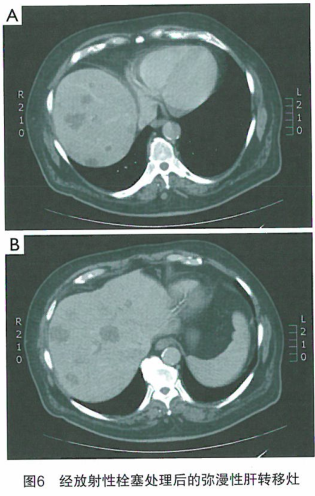

美国就医机构爱诺美康了解到,一位45岁的患布结肠癌的女性患者,伴有弥漫性肝转移灶,由于化疗的神经毒性导致化疗中止。其既往已经接受FOLFOX和FOLFIRI方案化疗。结合其肝脏转移灶呈弥漫性的特点和临床表现,建议她采用90-钇放射性栓塞治疗。虽然也可以选择化疗栓塞疗法,但现有的治疗结果表明90-钇放射性栓塞治疗在治疗小病灶方面疗效更好。